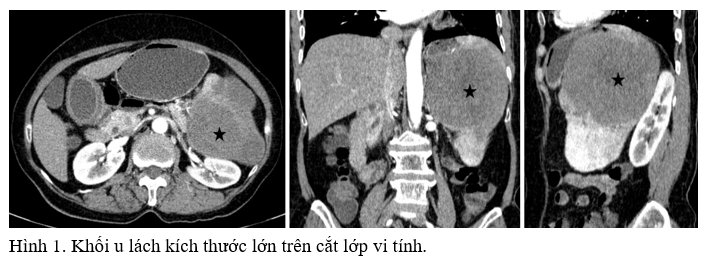

Bệnh nhân nữ 64 tuổi, vào viện vì đau vùng hạ sườn trái. Chụp cắt lớp vi tính ghi nhận lách lớn, trong nhu mô có nhiều khối choán chỗ bờ không đều, giới hạn khá rõ, đẩy lồi bao lách, chèn ép các tạng lân cận nhưng chưa thấy rõ xâm lấn (Hình 1). Khối lớn nhất có kích thước #10.5x10x9.5cm, trung tâm có hoại tử. Các khối này ngấm thuốc kém qua các thì. Vài tổn thương nhỏ tương tự ở gan, kích thước 7-15mm. Không phát hiện thêm bất thường nào khác. Bệnh nhân được chỉ định sinh thiết lách (Hình 2). Vì nguy cơ chảy máu khi sinh thiết lách, chúng tôi quyết định sử dụng kỹ thuật kim đồng trục có nút tắc đường hầm (Hình 3). Sau sinh thiết bệnh nhân đau tức nhẹ ở vùng hạ sườn trái, huyết động ổn định, không có tai biến tức thì và biến chứng muộn. Kết quả giải phẫu bệnh là angiosarcoma lách.